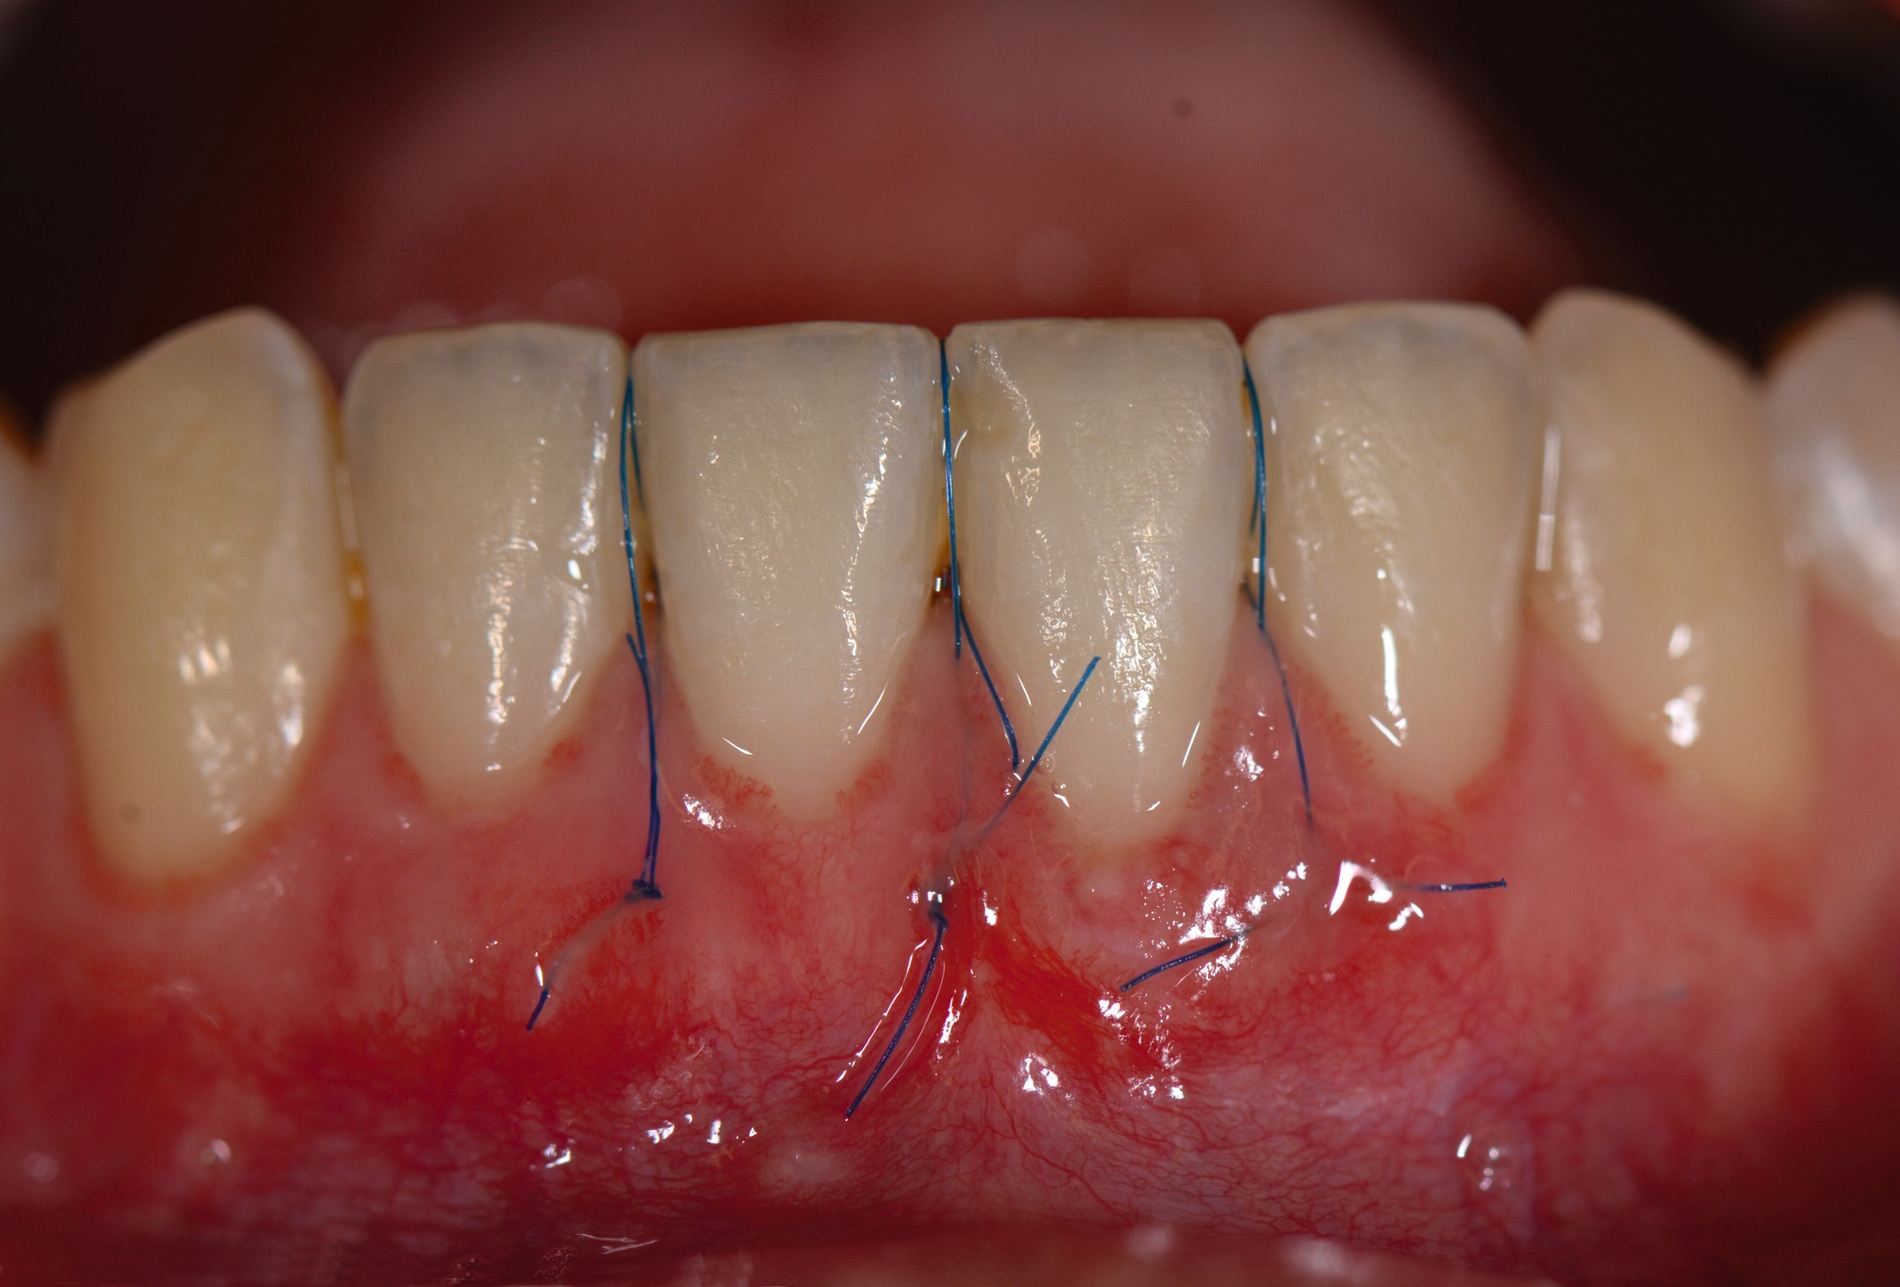

Das „klassische“ BGT wurde bereits in den 1970er-Jahren beschrieben und ist besonders verbreitet bei der Behandlung von gingivalen Rezessionen und der Weichgewebsaugmentation um Implantate. Das Transplantat wird durch eine sorgfältige Präparation unterhalb des Epithels vom lateralen und eher anterioren Gaumen gewonnen. Durch den Erhalt des bedeckenden Gewebes soll eine primäre Heilung sichergestellt werden. Die Höhe des Gaumendachs und somit die Entfernung zur Arteria palatina sowie die Dicke der Schleimhaut, vor allem über den palatinalen Wurzeln der Molaren zusammen mit den Rugae des anterioren Gaumens, sind die limitierenden Faktoren bei dieser Technik.

Trotz des Verbleibs des Epithels kann es zu sekundärer Wundheilung mit entsprechender Morbidität postoperativ kommen, besonders bei Techniken, die mehrere Inzisionen beinhalten, wie den sogenannten Trap-Door-Techniken, so dass sich die „Single-Incision-Technik“ durchgesetzt hat [Fickl et al., 2014]. Gegen eine übermäßige Blutung und postoperative Morbidität empfiehlt sich klinisch die routinemäßige Anwendung einer Verbandplatte, entweder in der Tiefziehtechnik oder präoperativ mittels eines Thermoplasts, so dass sich früh ein stabiles Blutkoagel bildet und die Wundheilung an der Entnahmestelle ungestört ablaufen kann. Dadurch wird die Morbidität klinisch deutlich reduziert. Das sBGT zeigt ästhetisch sehr gute Ergebnisse mit Blick auf Oberflächenstruktur sowie Farbe und kann unter anderem im Rahmen der Envelope- oder Tunneltechnik oder auch über einer Extraktionsalveole bewusst exponiert belassen werden, um zusätzlich befestigte Gingiva zu gewinnen.

Die Wundheilung nach dieser Technik erfolgt anders als beim sBGT immer sekundär, somit wurden bei Vergleichsstudien eine signifikant erhöhte Morbidität, Schwellungen und ein erhöhtes Nachblutungsrisiko beschrieben [Del Pizzo et al., 2002; Griffin et al., 2006], was jedoch bei entsprechender Versorgung des Gaumens umgegangen werden kann [Zucchelli et al., 2010]. Die Versorgung der Spenderregion kann mit Kollagenvlies, Cyanoacrylatkleber, Verbandplatte oder einer Kombination erfolgen. Dies kann die Morbidität deutlich reduzieren [Tavelli et al., 2019b]. Ein Vorteil von dBGT ist die Stabilität der Gewebedicke im Laufe der Zeit, was im Gegensatz zur beschriebenen Schrumpfung von sBGT steht, die häufig beobachtet wird [Zucchelli et al., 2018].